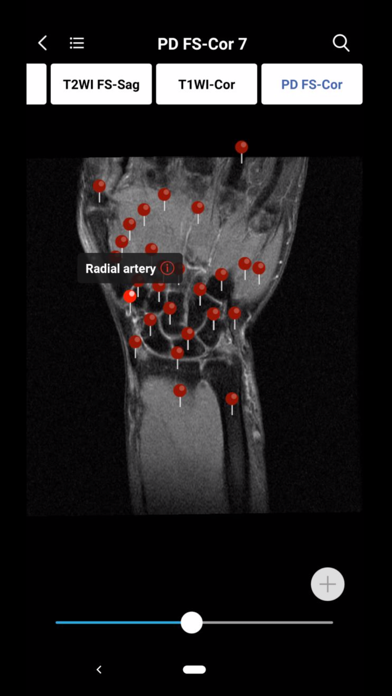

1. Normal imaging anatomy atlases which have the detailed structure labeling in coronal, sagittal, axis section. You can search any imaging structures conveniently at any time. Currently all imaging atlases’ images are JEPG format,  and they will be replaced by DICOM images very soon. This means you can to adjust the window width and window location of all images in the atlases. It's unbelievable!

2. MedImaging also includes 3D AR and 2D  anatomy pictures. When you slide to any image in the atlas, you can easily find the 3D and 2D anatomical pictures most relevant to the image. This means that you don't have to go through the anatomy textbooks if you forget the association between the general body anatomy and imaging anatomy. Just one click, you can build the intrinsic association between general anatomy and medical imaging. You'll understand medical imaging more efficiently and easily.